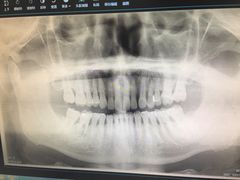

• 爱贝口腔·牙周诊疗·种植修复中心

• -爱贝口腔·牙周诊疗·种植修复中心

匿名用户 | 22-07-30